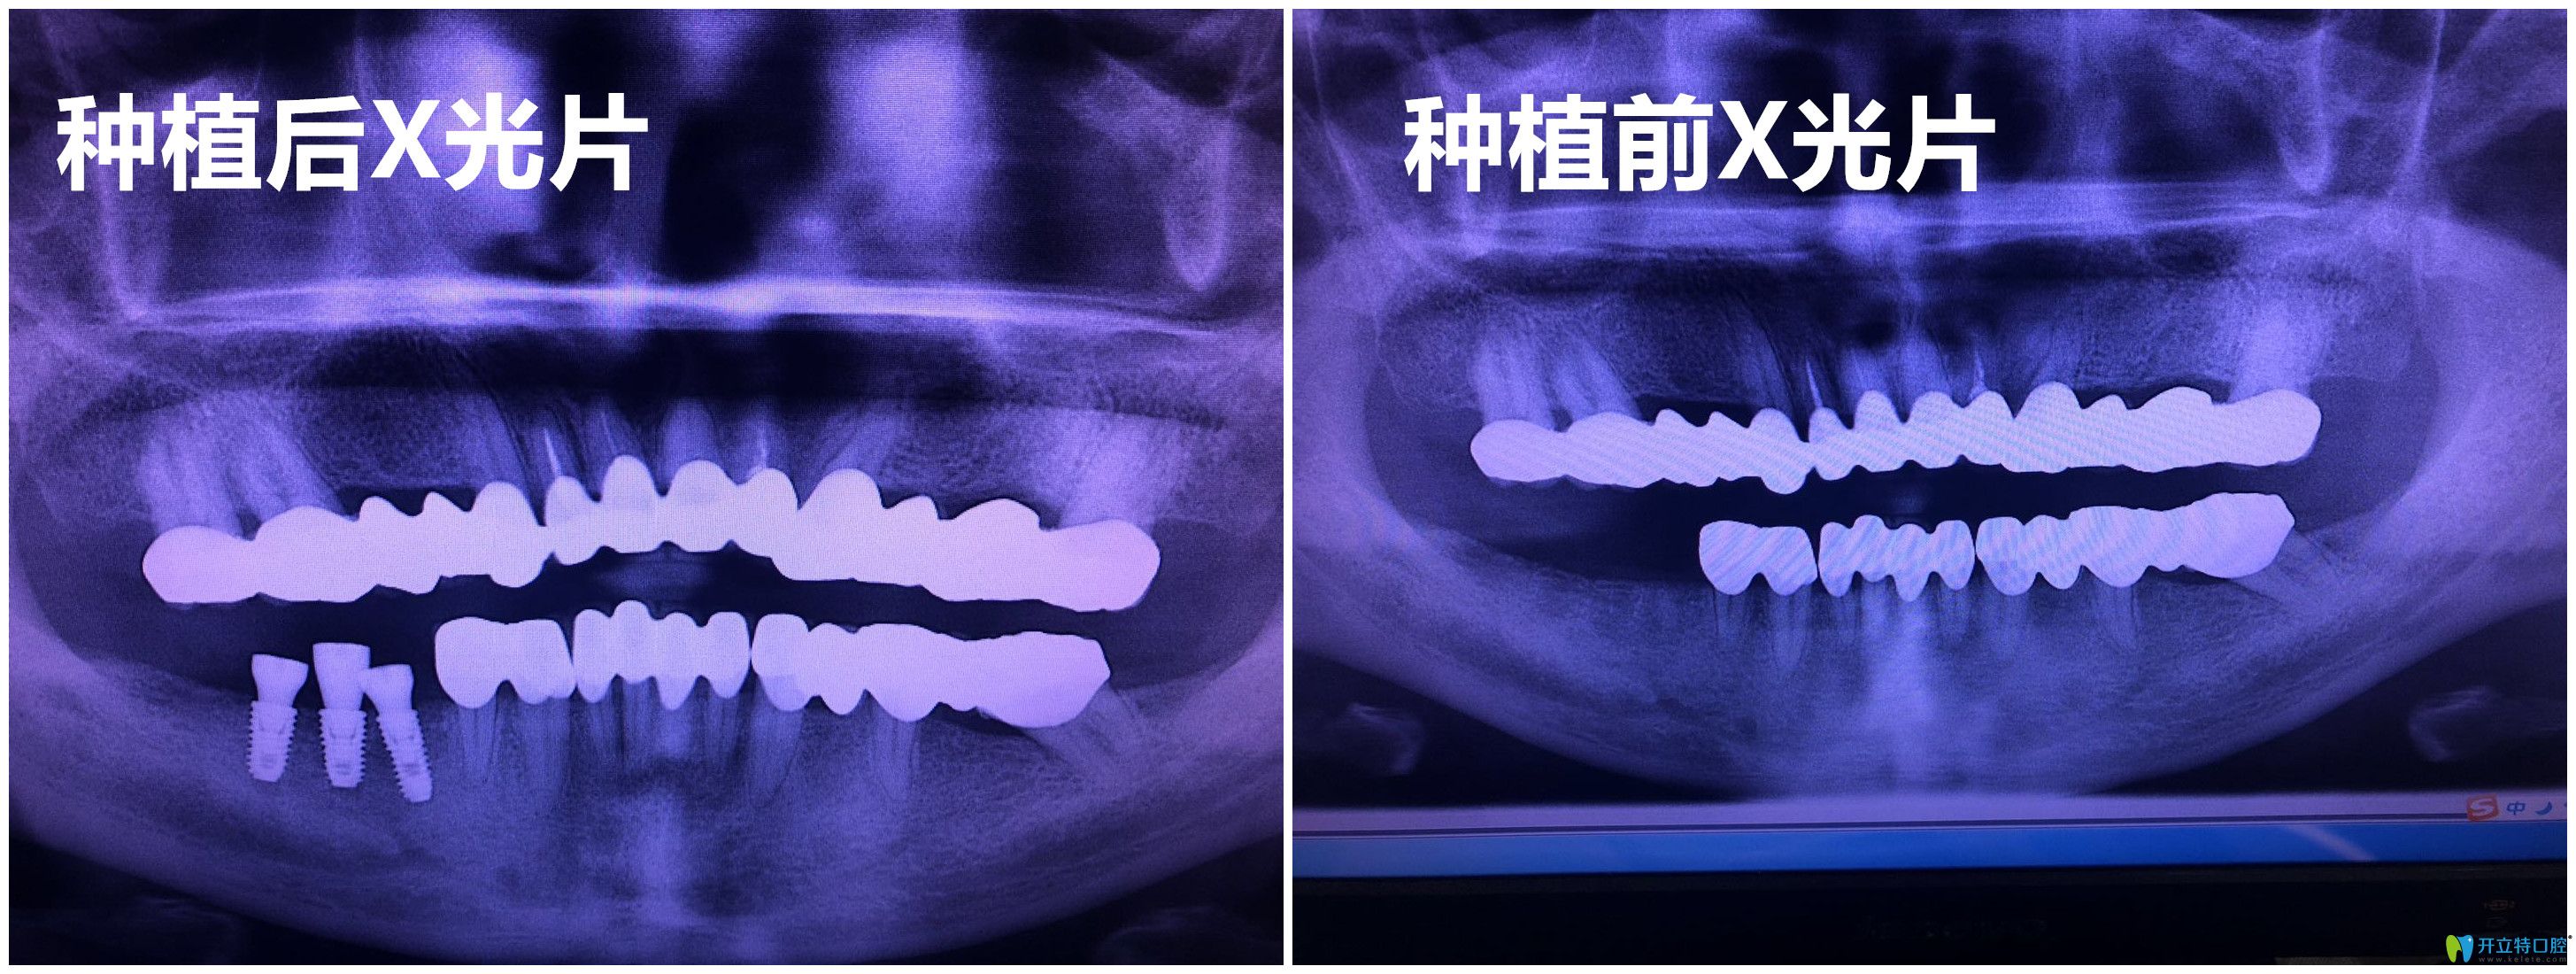

杭州逸盛口腔謝精文種植牙案例:

種植前:牙齒缺失三顆,平時(shí)吃東西特別不方便

種植后:在吃東西的時(shí)候沒有異物感,而且?guī)缀鯖]有什么需要忌口的,感覺和牙齒缺失時(shí)候沒有什么兩樣。

杭州逸盛口腔謝精文種植牙案例